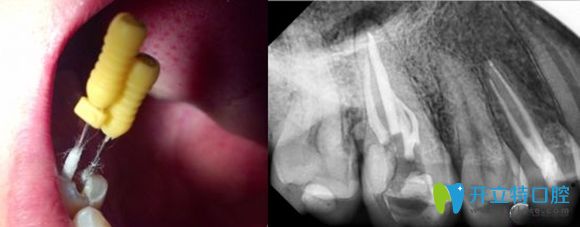

根管治療過程圖解

根管治療就是牙醫(yī)利用專用的器械,去除牙齒內(nèi)部感染的牙髓以及感染的牙本質(zhì),還有毒性分解產(chǎn)物,并進行適當?shù)南?,然后再進行嚴密充填根管,防止發(fā)生根尖周病變,或者是促進根尖周病變愈合的一種治療方法。

牙齒根管治療科普圖

別看總結起來就一段話,實際上根管治療的程序可是非常復雜的,需要格外的細致。醫(yī)生操作起來既費時又費力,還不能一次診療即可完成,通常從初診到治療結束,需要3-4次的復診。

牙齒根管治療過程中圖片

根管治療后的X線片影像圖